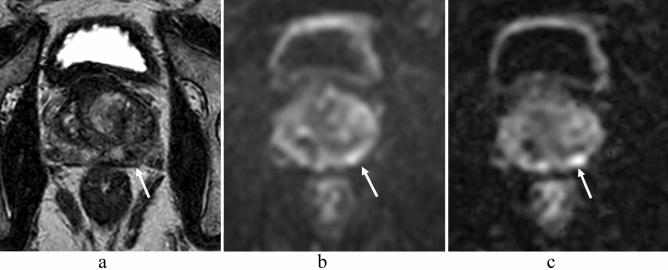

在 3.0T 下比较单激发 EPI 和多激发 EPI 在前列腺 DWI 中的应用。

Comparison of single-shot EPI and multi-shot EPI in prostate DWI at 3.0 T.

In prostate MRI, single-shot EPI (ssEPI) DWI still suffers from distortion and blurring. Multi-shot EPI (msEPI) overcomes the drawbacks of ssEPI DWI. The aim of this article was to compare the image quality and diagnostic performance for clinically significant prostate cancer (csPC) between ssEPI DWI and msEPI DWI. This retrospective study included 134 patients with suspected PC who underwent 3.0 T MRI and subsequent MRI-guided biopsy. Three radiologists independently assessed anatomical distortion, prostate edge clarity, and lesion conspicuity score for pathologically confirmed csPC. Lesion apparent diffusion coefficient (ADC) and benign ADC were also calculated. In 17 PC patients who underwent prostatectomy, three radiologists independently assessed eight prostate regions by DWI score in PI-RADS v 2.1. Anatomical distortion and prostate edge clarity were significantly higher in msEPI DWI than in ssEPI DWI in the three readers. Lesion conspicuity score was significantly higher in msEPI DWI than in ssEPI DWI in reader 1 and reader 3. Regarding discrimination ability between PC with GS ≤ 3 + 4 and PC with GS ≥ 4 + 3 using lesion ADC, AUC was comparable between ssEPI DWI and msEPI DWI. For diagnostic performance of csPC using DWI score, AUC was comparable between msEPI DWI and ssEPI DWI in all readers. Compared with ssEPI DWI, msEPI DWI had improved image quality and similar or higher diagnostic performance.

摘要

在前列腺 MRI 中,单次激发 EPI(ssEPI)DWI 仍然存在失真和模糊的问题。多激发 EPI(msEPI)克服了 ssEPI DWI 的缺点。本文旨在比较 ssEPI DWI 和 msEPI DWI 对临床显著前列腺癌(csPC)的图像质量和诊断性能。这项回顾性研究纳入了 134 名疑似 PC 患者,他们均接受了 3.0T MRI 检查和随后的 MRI 引导活检。三位放射科医生独立评估了病理证实的 csPC 的解剖失真、前列腺边缘清晰度和病灶显影评分。还计算了病灶表观扩散系数(ADC)和良性 ADC。在 17 名接受前列腺切除术的 PC 患者中,三位放射科医生通过 PI-RADS v 2.1 对 8 个前列腺区域的 DWI 评分进行了独立评估。三位读者均认为 msEPI DWI 的解剖失真和前列腺边缘清晰度明显高于 ssEPI DWI。读者 1 和读者 3 认为 msEPI DWI 的病灶显影评分明显高于 ssEPI DWI。对于使用病灶 ADC 区分 GS≤3+4 和 GS≥4+3 的 PC,ssEPI DWI 和 msEPI DWI 的 AUC 相当。对于使用 DWI 评分诊断 csPC 的性能,所有读者均认为 msEPI DWI 和 ssEPI DWI 的 AUC 相当。与 ssEPI DWI 相比,msEPI DWI 的图像质量得到了改善,且诊断性能相似或更高。